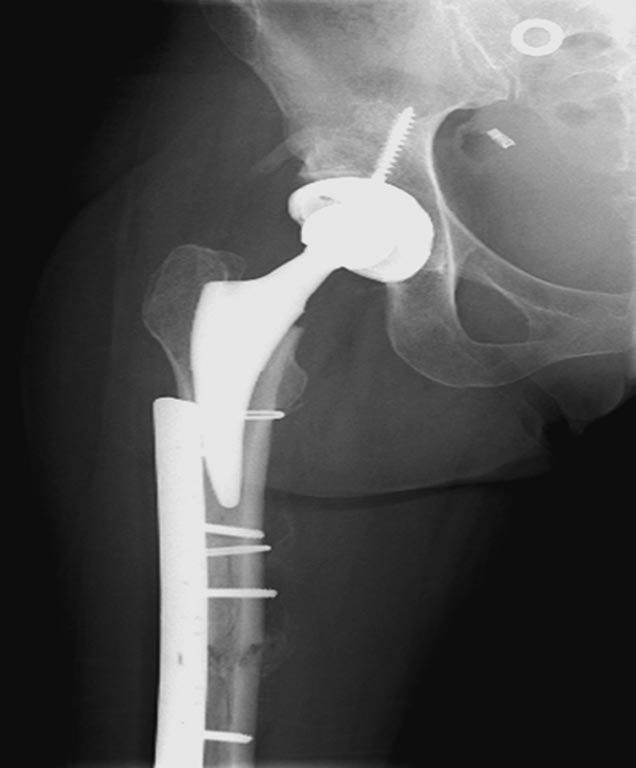

На 25 день с момента травмы операция на Jackson table с боковым обширным доступом. Удаление стержней с местной обработкой. В тазобедренном суставе удаление головки, на дне вертлужной впадины полная отслойка хряща. Вертлужный компонент с одним винтом и короткая ножка - Fitmore press fit stem. На второй день однократно доза радиации для профилактики гетеретопической оссификации. Послеоперационный период без температуры. Выписана. Нагрузку разрешили на левой стороне, а полная в 3 мес. Здесь снимки при амбулаторном наблюдении: послеоперационно, 2 мес, 3 мес и 6 мес. Нагрузка полная, отсутствует хромота, и нет жалоб.